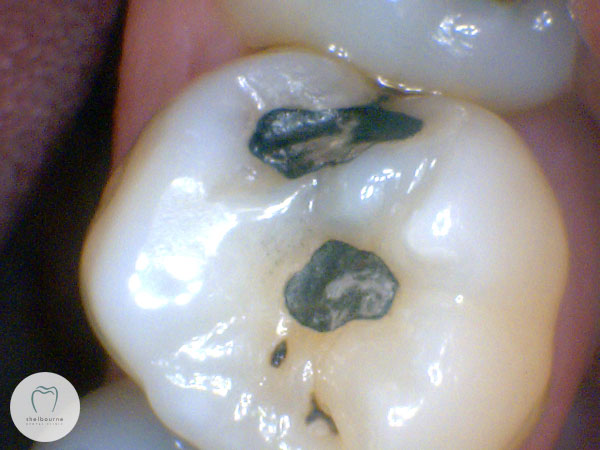

The patient, who I was seeing for the first time, reported significant pain from the upper left teeth. Nothing was obviously visible, no teeth were tender to pressure or biting. Here’s a photo of the area. Two small fillings in this tooth, but it looks fine.

So having found the damage, and numbed the tooth to ensure it’s not sensitive to the water spray, I polished out the existing filling and a small portion of tooth. You can quite clearly see the decayed area now. Unfortunately this decayed area just kept going, and the outlook for this tooth isn’t great.

But go back and look at the first photograph again. There really was no sign of decay visible, and yet now we’re at the point of doing a complicated root canal treatment at a minimum, or quite possibly losing the tooth. Naturally I want to find something like this well before it gets to the point of no return. X-rays aren’t fool-proof either, but they’re another piece of the puzzle that lets us build up as comprehensive a picture as possible of your dental health, helping us make the treatment choices that most benefit you.